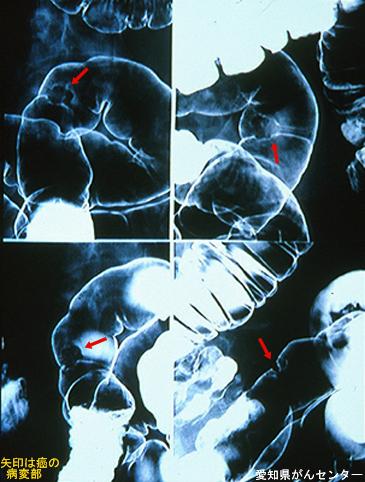

Criteria of Hist.ClassificationMalignant epithelial tumor/Adenocarcinoma

LocationLarge intestine(Colon)/Sigmoid colon

Technique, MethodX-ray

Macroscopic TypesType 0/IIa (IIa+IIc) Superficial elevated and depressed type

Size15 - 19

Depth of Tumor Invasionsubmucosa